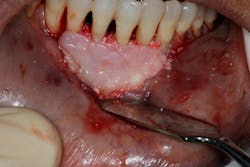

- Appropriate scaffolding material, biologic agent, and/or cell occlusive barrier for periodontal regeneration (figure 4)